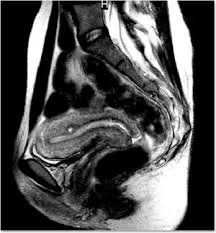

Chụp cộng hưởng từ (MRI) khung chậu là một xét nghiệm hình ảnh học sử dụng một máy có nam châm mạnh và sóng vô tuyến để tạo ra hình ảnh của cơ quan nằm trong khu vực giữa khung xương chậu. Các cấu trúc này bao gồm bàng quang, tuyến tiền liệt ở nam, buồng trứng và tử cung ở nữ, các hạch bạch huyết, ruột già, ruột non và xương chậu. Do bị che lấp bởi khung xương, chụp cộng hưởng từ là phương tiện lý tưởng cho việc khảo sát các bệnh lý tại đây.